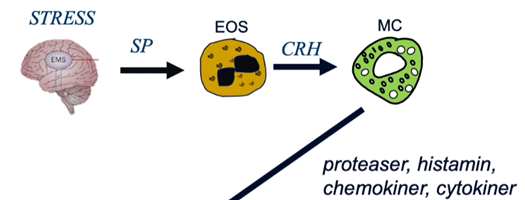

Vilken neuroimmun signalering kan ske vid IBD som kan leda till störd barriär?

- Vid stress utsöndras substans P från hjärnan som binder in till eosinofiler (viktiga vid barriären vi inflammatorisk tarmsjukdom) som aktiveras och utsöndrar CRH som binder till mastceller som aktiveras och utsöndrar granulae à proteaser, histamin, kemokiner och cytokiner vilket rekryterar inflammatoriska celler och ger vävnadsförändring med ökad genomsläpplighet vilket ger ökad passage från lumen med ökad aktivering av mastceller, T-celler osv, alltså ett ökat inflammatoriskt svar